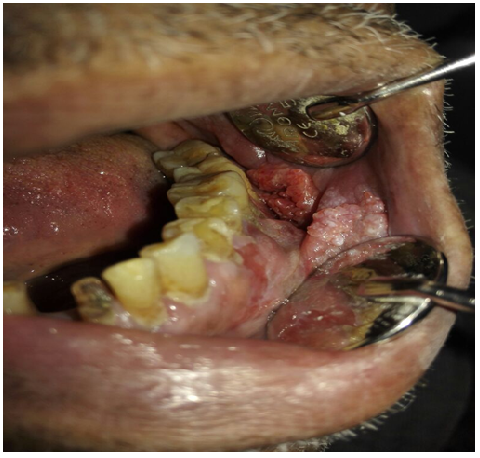

85 years old male came to the clinic suffering from painful ulcer in the left buccal mucosa related to the lower first and second molars. The patient stated that this ulcer appeared three months ago and was preceded by long standing reddish white lesion. The related molars have grade 3 mobility upon clinical examination.